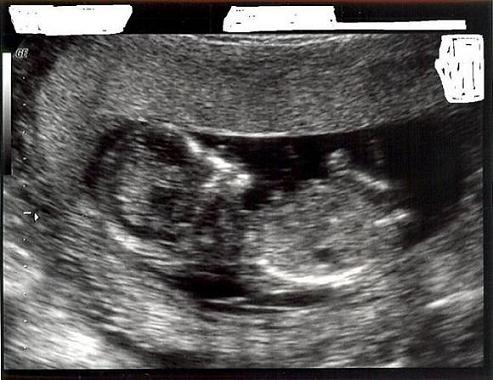

very interesting...can you help me guess with my 12 week sono pic? Girl? I always thought that part was part of the baby's leg.

Image Attachment(s):

Yay! how fun? Well, there r a lot more pics if u follow the link in the article to compare it to but just judging by the two examples in the original article I think I would guess boy... The angle looks a lot like the author's boy sono.

GIRL! The angle is less than 30 degrees from the spine.

Yeah, actually I think I agree. The baby looks a little on its side so that was throwing me off but I think I change my guess haha. OMG I am gonna SCRUTINIZE my 12 week sono...

You have to careful that the spine is not curved. DS's nub looked girly in the shot I had of him because his spine was curled.